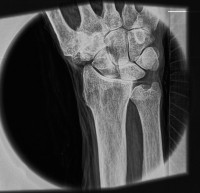

| Снимок запястья, демонстрирующий способность системы «видеть» мягкие ткани. Источник: Luis Velásquez-García et al. |

Рентгеновские аппараты не дают возможности получать снимки мягких тканей без контрастных агентов наподобие бария, и разрешение таких снимков невелико. Разработка специалистов Массачусетского технологического института и Массачусетской больницы общего профиля обещает кардинальные перемены: гораздо более детальные снимки, в том числе мягких тканей, без контрастных агентов. К тому же аппарат из МТИ компактнее традиционных и выдает меньшую дозу облучения.